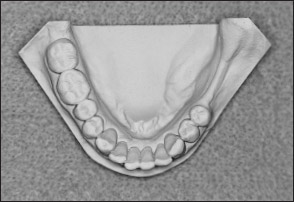

• Kennedy Class II arch: Displays a unilateral edentulous area located posterior to the remaining natural teeth (Figs 1-13 and 1-14).

Fig 1-13 Maxillary Kennedy Class II arch.